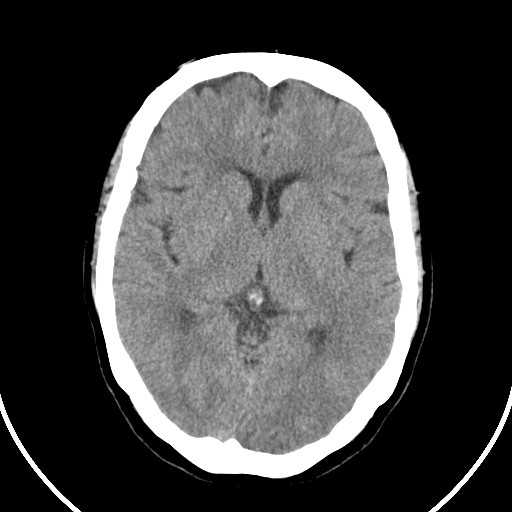

标题: CT21850:女,56岁,右中指淤肿,右手麻痹1天

女,56岁,右中指淤肿,右手麻痹1天

右侧基底节多发小梗塞

右基底结区腔梗

右侧基底节区腔隙性脑梗塞

右侧基底节多发腔梗!

双侧侧脑室额角旁对称性略低密度影,边缘模糊,无占位效应,考虑轻度脑白质稀疏症(病人有高血压吗).,右枕叶低密度影多为伪影,不放心薄扫一下.

考虑脑白质病。

考虑脑白质病

右枕叶条状低密度影不应该忽略可能极具意义